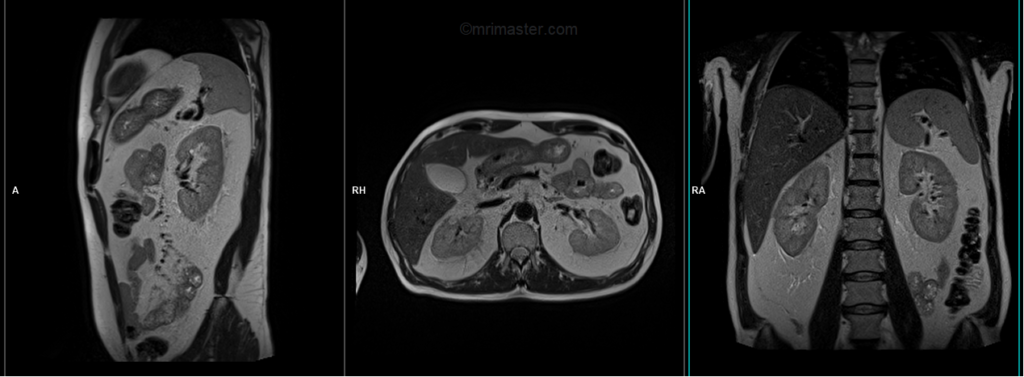

A three-plane T2 HASTE localizer must be taken initially to localize and plan the sequences. These fast, single-shot localizers usually have an acquisition time of less than 25 seconds, which is excellent for localizing abdominal structures.